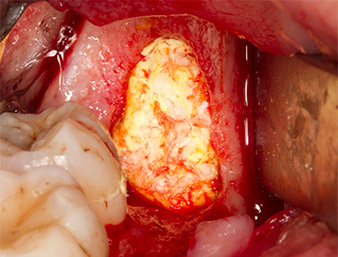

Frammenti ossei

Fig. 13: I frammenti ossei dall'area dell'intervento sono stati conservati in una soluzione salina sterile.

Successivamente, il tessuto osseo autogeno (Fig. 13) è stato posizionato nell'alveolo e nel circostante difetto osseo (Fig. 14). Un vello di collagene ricopriva i frammenti di osso fino a livello dell'osso come protezione per il nervo esposto (Fig. 15). Per chiudere il tessuto molle aperto sono state utilizzate suture con filo in Vicryl, USP 4.0 (Fig. 16). Dopo l'operazione sono stati prescritti una preparazione di Ibuprofene (Seractil 400 mg, 3x1) e un antibiotico costituito da amossicillina e acido clavulanico (Augmentin 1 g, 2x1).

porzione apicale dell'alveolo

Fig. 14: La porzione apicale dell'alveolo è coperta con il tessuto autogeno.